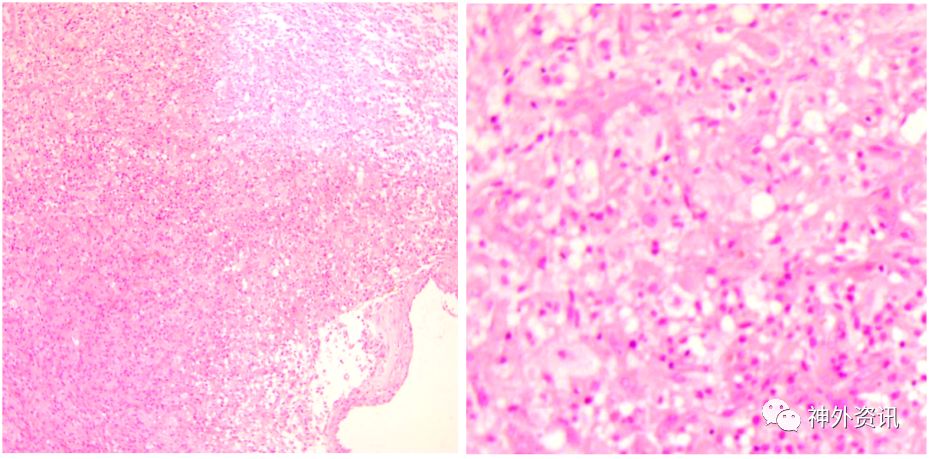

术后常规病理报告:(右额颞)胶质母细胞瘤,IDH野生型,WHO IV 级(图5)。

图5. 石蜡切片HE染色,提示胶质母细胞瘤。

免疫组化结果:PTEN +,GFAP +,Ki-67 30%,NF -,NSE +,P53 散在+,MGMT +,Olig2 散在+,ATRX +,BRAF-V600E -,H3K27M -,IDH1 -,S-100 -。

分子病理结果:

突变负荷(TMB):56

微卫星不稳定(MSI):0.13%

染色体拷贝数变异(CNV):1.36%